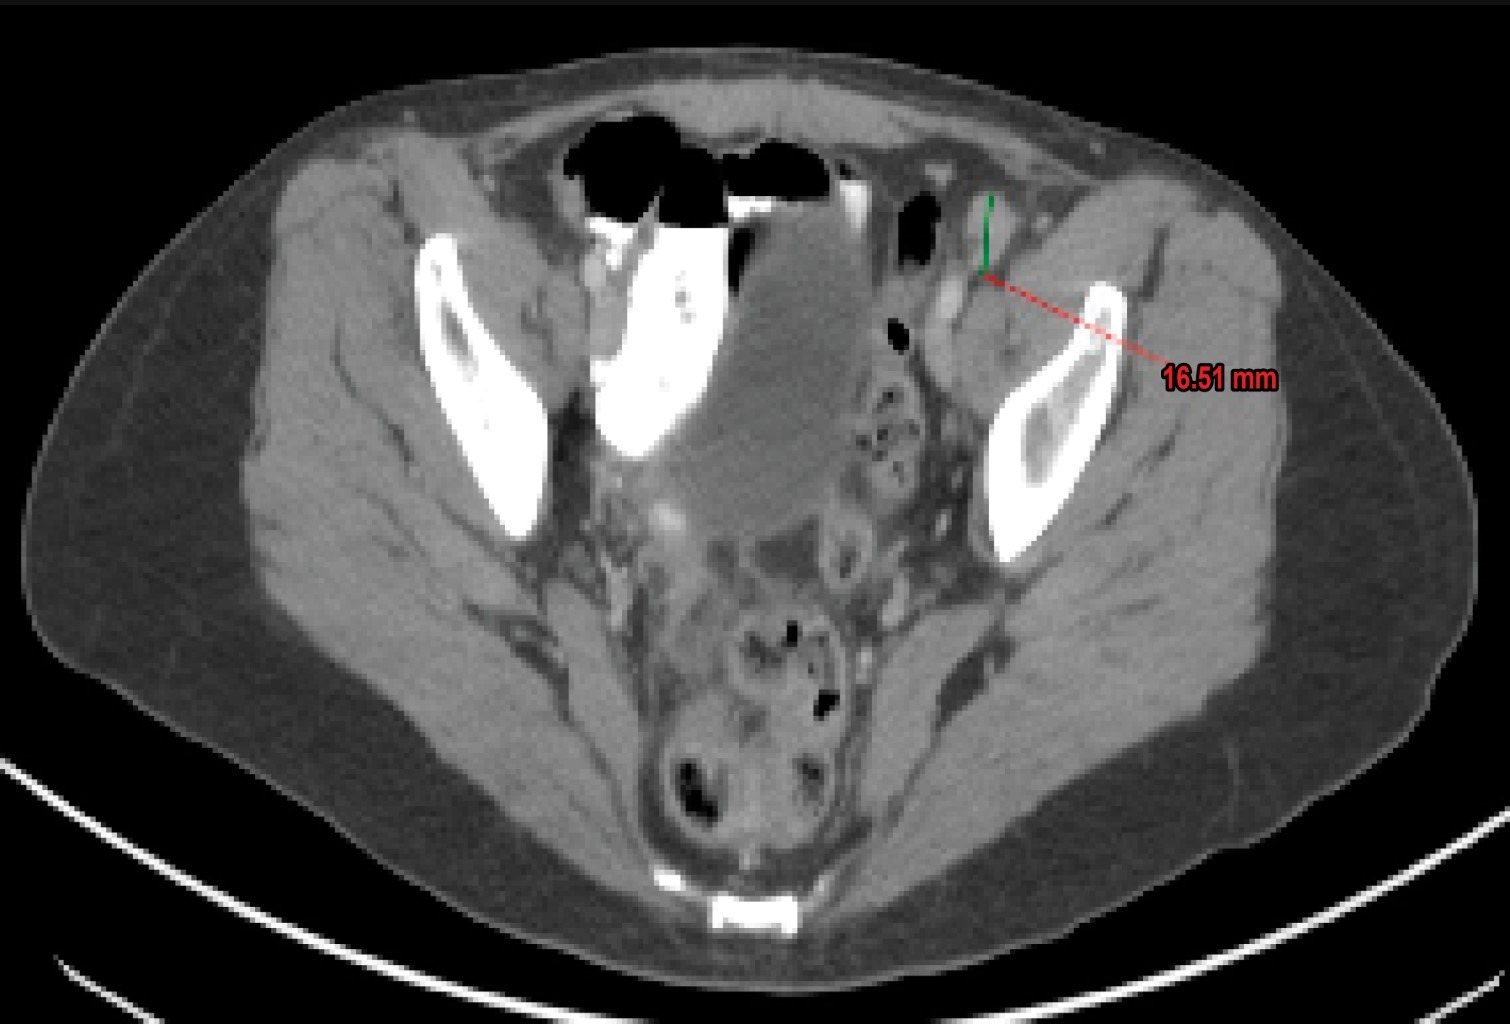

Femenino de 54 años con diagnóstico de cáncer de ovario estadio IIIC que había sido sometida a citorreducción quirúrgica y quimioterapia sin evidencia de recurrencia, se presenta en el servicio de urgencias con un síndrome cerebeloso subagudo. El estudio de imagen descarta alteraciones estructurales, punción lumbar con pleocitosis linfocitaria, hiperproteinorraquia y anti-Yo positivo, con actividad tumoral inguinal confirmada por PET-CT.

Inicia seis días previos a su ingreso con diplopía bilateral, mareo e inestabilidad postural. A su ingreso se presenta alerta con nistagmus multidireccional no fatigable, trofismo y fuerza muscular normal, destaca arreflexia y marcha atáxica con signo de Romberg presente. Se realiza resonancia magnética que se reporta normal con subsecuente punción lumbar, no se reportan hallazgos relevantes en citología y citoquímica, la paciente presenta anticuerpos anti-Yo positivos (≥ 1:10), por lo que se establece síndrome paraneoplásico con recurrencia de la enfermedad confirmada por tomografía por emisión de positrones a nivel ganglionar inguinal izquierdo (Figuras 1 y 2).

Figura 2